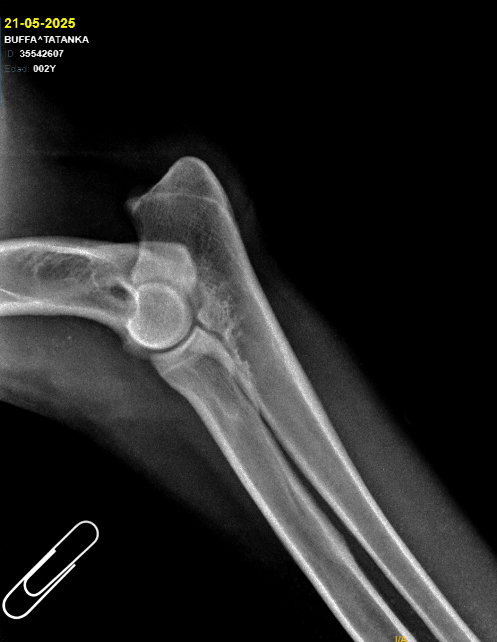

Fecha de nacimiento: 21/05/2023

Coat: Long

Cadera Codos:

HD A / ED 0/0

DM: N/N MDR1 +/+

Developing:

Altura: 68cm

Weight: -

Alias Tatanka, a happy dog, always seeking contact and affection, along with his brother, they are partners in mischief. He's very vocal when communicating and howling! High energy, determined, clumsy, but intelligent.

Tatanka is a very well-behaved male, with a robust build, good pigmentation, excellent coat, harmonious proportions, and a strong forehead. His head is heavy and beautifully proportioned. He is always willing to greet everyone and socialize, a bit stubborn at times, but generally very obedient. He loves water!